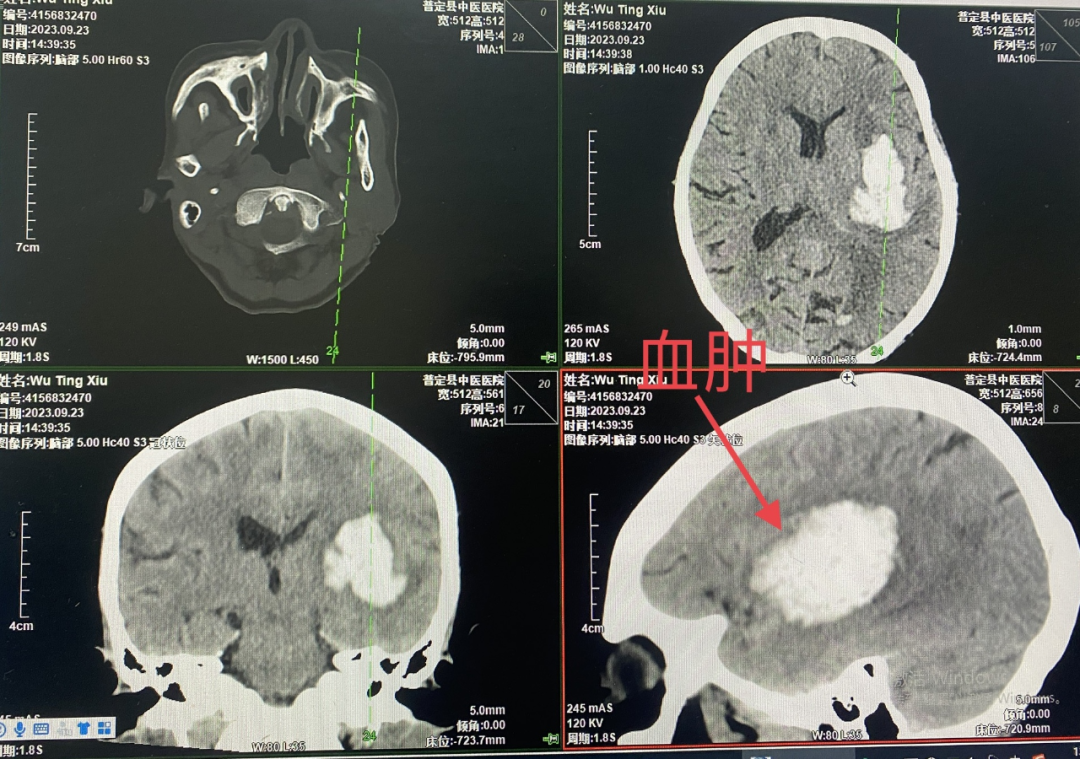

73岁的吴奶奶,入院前一个小时突然出现言语不利伴右侧肢体无力,被家属紧急送到我院就诊,入院时意识不清,嗜睡,右侧肢体偏瘫,查头颅CT提示:左侧基底节区出血,量约30+ml,家属考虑患者年龄大,既往基础疾病多,体质瘦弱,手术风险高,要求药物非手术观察治疗。住院期间患者意识障碍加重呈浅昏迷状,鼾样呼吸,剧烈呕吐,再次复查头颅CT提示出血无明显增加,血肿腔周围水肿加重,外二科神经外科组医生当机立断,建议行手术治疗,充分综合考虑患者的身体情况,详细向家属沟通各种手术方式,为缩短麻醉时间,减少手术创伤,降低手术风险,手术方式建议选择微创颅骨钻孔血肿穿刺置管引流术或小切口小骨窗开颅血肿清除术,在告知各种术式利弊及风险后,家属最终决定选择小切口小骨窗开颅血肿清除术。

入院6小时CT